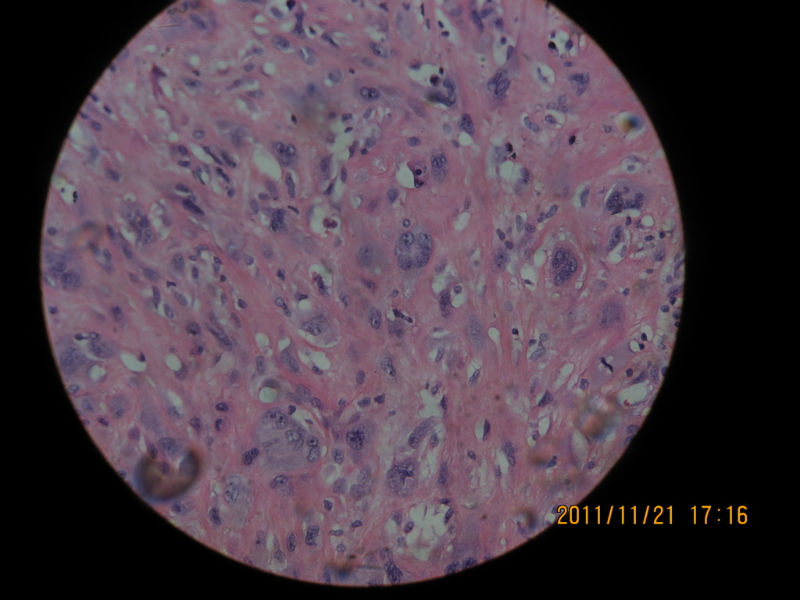

男性,82岁,声带肿物

粘膜下可见怪异的细胞,仍是息肉。

肿瘤大小?肉瘤样癌,恶黑,横纹肌肉瘤,滑膜肉瘤等也需要鉴别

息肉。在声带息肉中容易见到这种怪异细胞,不要过诊断为恶性,让随访观察吧。

感觉很安静,考虑良性。

息肉

结合免疫组化结果最后诊断为恶性纤维组织细胞瘤

诊断恶性纤维组织细胞瘤可以的。那么异型的细胞,息肉不放心。

是恶纤组啊?我还考虑血管源性肿瘤呢。

学习,黏膜下见多形性和异形性明显的细胞弥漫分布,核分裂可见,并见凋亡细胞,首先考虑肉瘤样癌,非典型黄色瘤要考虑,当然组化帮助了我们,临床病史及喉镜检查情况是我们要搜寻的信息。